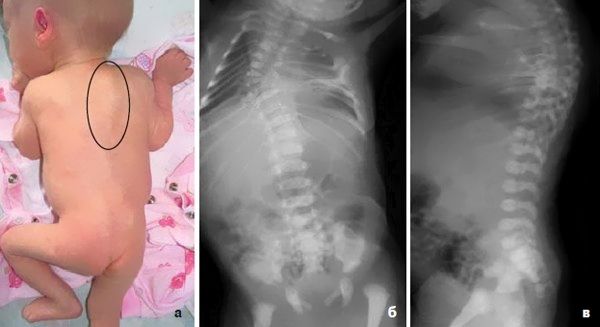

Сколиотическое искривление становится заметным, когда угол отклонения превышает 10°. Если посмотреть на человека спереди, можно заметить асимметрию ушных раковин. Со спины проявляется асимметрия лопаток и плеч, а также небольшое смещение головы в сторону. На более поздних стадиях болезни может наблюдаться асимметрия костей черепа.

Рентген верхних позвонков является обязательным исследованием при шейном сколиозе. На рентгеновском снимке четко виден угол искривления, что помогает определить степень патологии. Рентгенологическое исследование назначается как на ранних, так и на поздних стадиях заболевания.